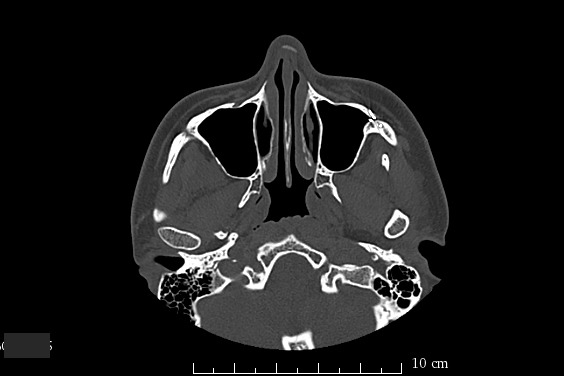

A. 치과에서 촬영하는 사진의 가장 대표적인 것은 '파노라마'라는 사진임. 서서 손잡이를 잡고 있으면 삐~ 같은 소리가 나면서 한 바퀴 돌아가서 나오는 사진이 바로 파노라마.

바로 이렇게 나오는 사진임

치과에서 나오는 파노라마 사진은 왼쪽과 오른쪽이 반대임. 위에 나오는 사진을 봤을 때

왼쪽=실제 우리 얼굴의 오른쪽

오른쪽=실제 우리 얼굴의 왼쪽

이거임. 그러니까 치과에서 선생님이 자꾸 반대로 말한다고 당황하지 말길